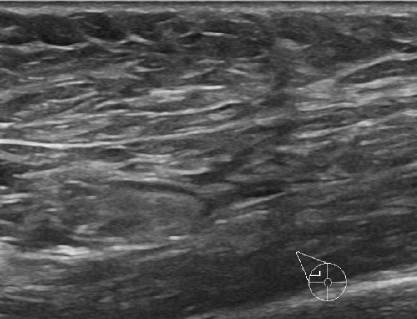

4.1.4 Ultrasound breast cancer

Breast cancer has gained significant attention in recent times due to its high mortality rate and the increasing number of reported cases. Using the ultrasound imaging technique makes it possible to observe the tissue distribution for cancer visual detection, making it an early detection alternative to diminish the public health impact. The dataset444https://www.kaggle.com/datasets/sabahesaraki/breast-ultrasound-images-dataset used in this work contains 780 images with three categories: benign with 442 images, malignant with 206, and normal with 132. The scans were collected from 600 women between 25 and 75 years old. It is a highly unbalanced dataset with different image sizes, having an average of 500×500500500500\times 500500 × 500 pixels [38]. Figure 5 showcases examples from each of the three described classes.

Refer to caption

(a) Normal

(b) Benign

(c) Malign

Figure 5: Breast ultrasound images.